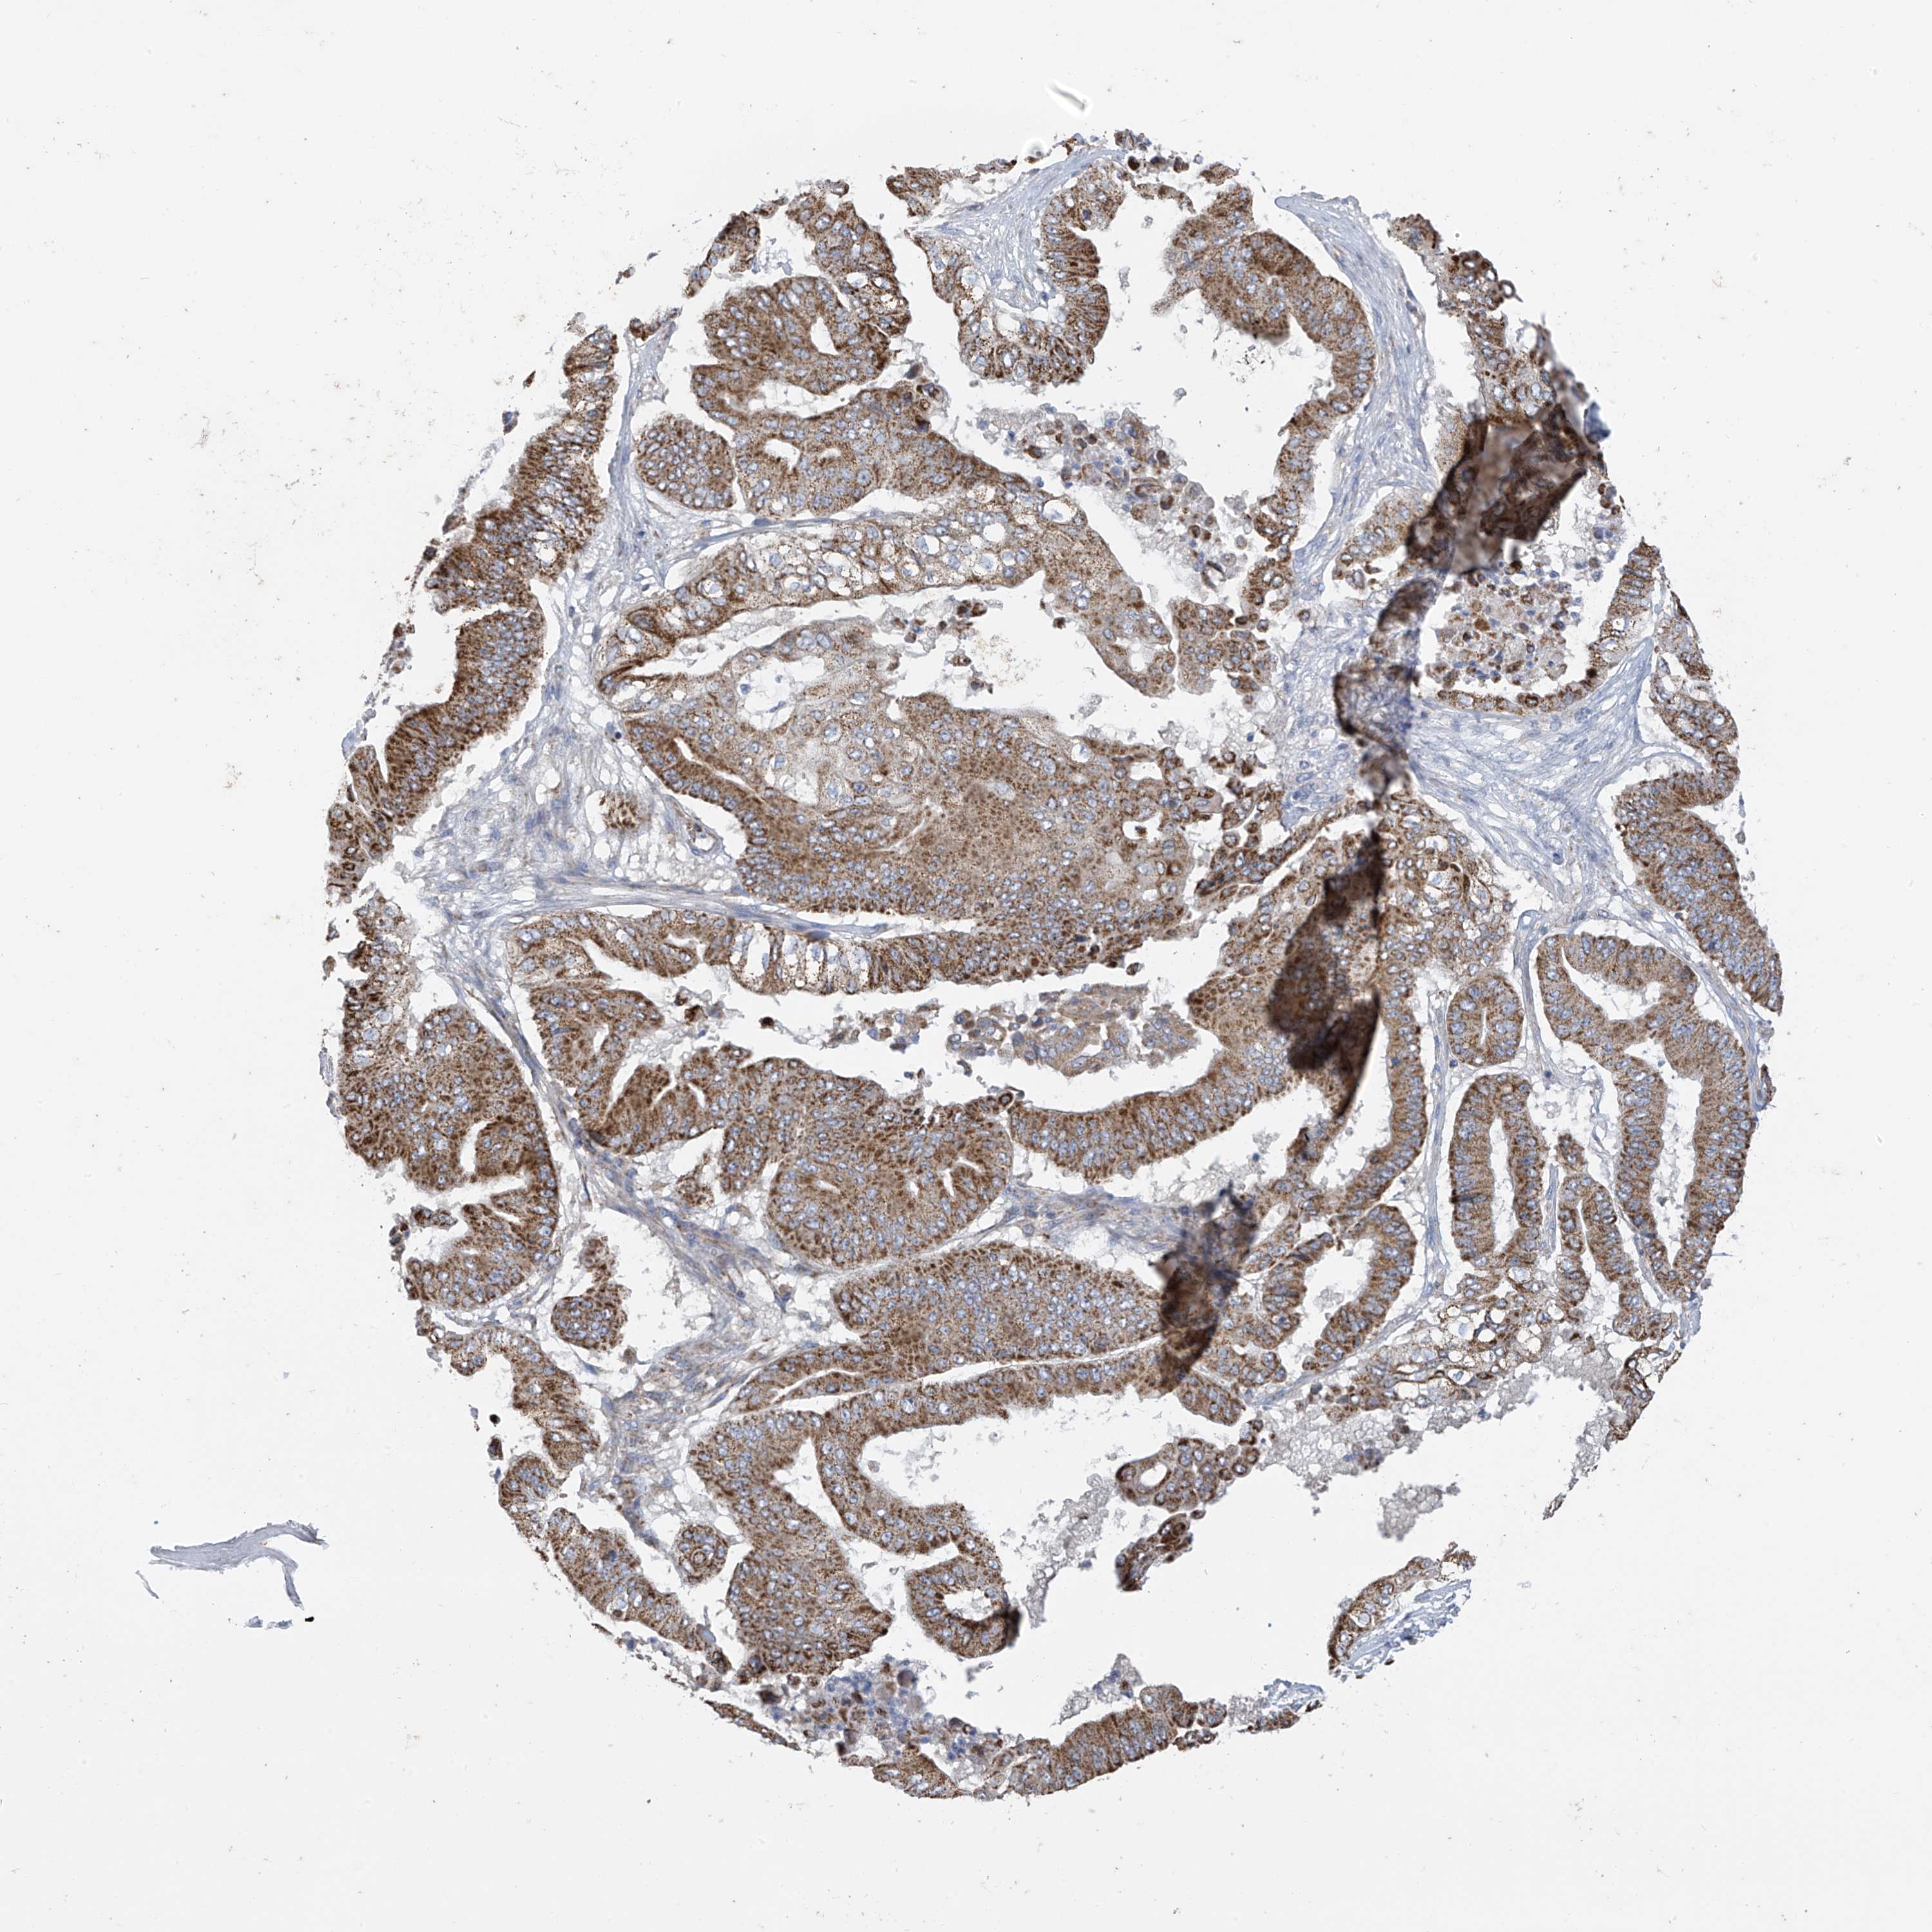

PANCREATIC CANCER - Protein expressioni

A mouse-over function shows sample information and annotation data. Click on an image to view it in a full screen mode. Samples can be filtered based on level of antibody staining by selecting one or several of the following categories: high, medium, low and not detected. The assay and annotation is described here.

Note that samples used for immunohistochemistry by the Human Protein Atlas do not correspond to samples in the TCGA dataset.

Antibody stainingi

Antibody staining in the annotated cell types in the current human tissue is reported as not detected, low, medium, or high, based on conventional immunohistochemistry profiling in selected tissues. This score is based on the combination of the staining intensity and fraction of stained cells.

Each image is clickable and will lead to virtual microscopy that enables deeper exploration of all samples and also displays staining intensity scores, fraction scores and subcellular localization as well as patient and tissue information for each sample.

Antibody HPA034602

Antibody HPA034603

Antibody CAB033424

Staining

High

Medium

Low

Not detected

Intensity

Strong

Moderate

Weak

Negative

Quantity

>75%

75%-25%

<25%

None

Location

Nuclear

Cytoplasmic/membranous

Cytoplasmic/membranous,nuclear

Adenocarcinoma, NOS